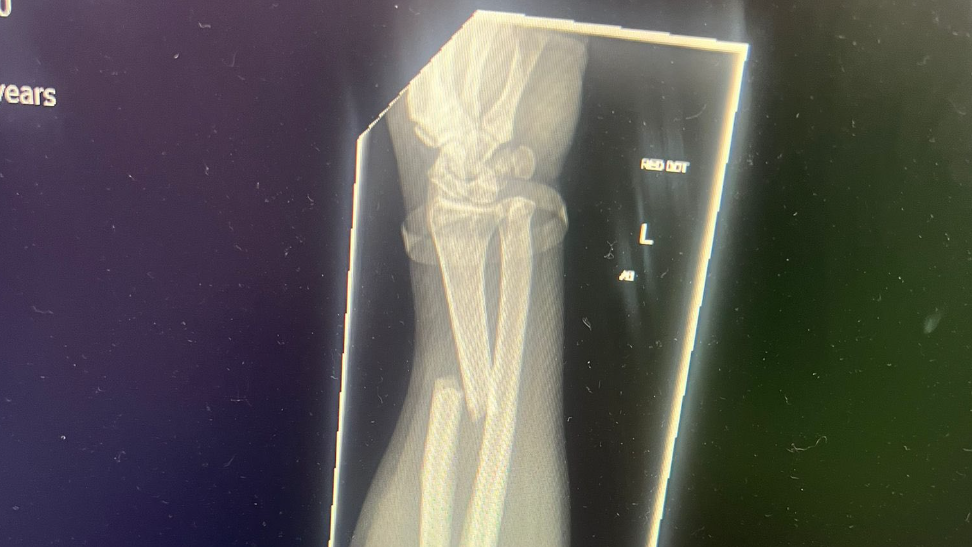

Isle of Man TT rider Mark Parrett has confirmed that he faces surgery following a fracture to his left arm sustained in last Friday’s dramatic bird strike during the Superstock race.

Updating supporters via Facebook, Parrett revealed that surgery is necessary to repair significant damage to the radius bone.

“Currently laid up and already getting bored watching TT 2025 reviews on repeat,” Parrett said. “Unfortunately, the update on my arm isn’t great -a significant fracture to the radius bone that will require surgery, including plates and screws. I’m hoping to go in for the operation on Friday.”

The GoFundMe page explained his injury: "Mark suffered a displaced fracture of the radius bone in his left arm, requiring open reduction and internal fixation - in simpler terms, a small titanium upgrade. Unfortunately, this is beyond even the skills of our trusty Slick to fix this time.